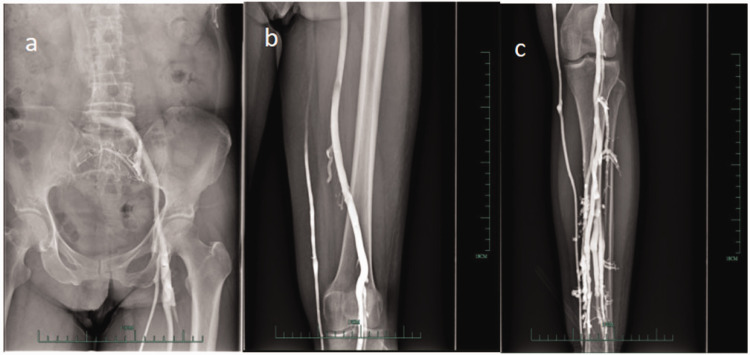

This study explores effective treatment methods for chronic secondary lymphedema after radical cervical cancer surgery combined with pelvic lymphadenectomy. In cases where conservative treatment was ineffective, we investigated whether multiple injections of indocyanine green can effectively improve the outcomes of lymphatic-venous anastomosis under microscopy. Preoperative lymphatic imaging was used to localize functional vessels, guiding distal left lower limb lymphatic reconstruction. Intraoperatively, supermicroscopy (40×) and real-time indocyanine green imaging enabled eight end-to-end anastomoses between 0.5- and 1.3-mm lymphatic capillaries and subcutaneous veins. Each anastomosis took ≤30 min, with intraoperative lymphangiography confirming patency. Immediate postoperative lymphatic diversion to veins was observed. By day 3, reconstructed pathway efficiency reached 83% of the healthy side, with visual analog scale pain scores decreasing from 5 to 2. At 3-6 months, mid-thigh and calf circumferences reduced progressively; ultrasound confirmed edema resolution and complete cessation of exudation. High-precision multipoint supermicrosurgical anastomosis achieved anatomical and functional reconstruction of chronic secondary lymphedema, overcoming traditional size and functional limitations. Innovations included multipoint design to prevent reobstruction and dynamic imaging-guided precision. This case establishes a radical treatment strategy for chronic secondary lymphedema.